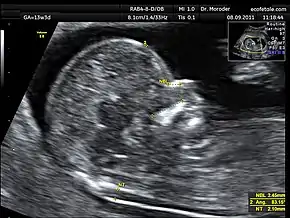

Benacerraf pioneered the field of "genetic sonography"[3] with her discovery that nuchal fold thickness–the distance between the occipital bone and the surface of the overlying skin at back of the neck–was a reliable metric for second-trimester diagnosis of Down syndrome.[1][2][4][5] Benacerraf's advocacy of ultrasound as a less intrusive alternative to amniocentesis was initially criticized.[1] She recalled, "People thought I was this crazy lady in private practice who thought that measuring the neck was related to Down syndrome. So I was almost booed off the stage a couple of times."[2] However, a flurry of independent studies in the late '80s and '90s affirmed the diagnostic value of fetal ultrasound, and the nuchal translucency scan (pictured), the first-trimester analog of the nuchal fold thickness test, is now a standard component of prenatal aneuploidy screening.[6][7][8] Benacerraf also made major contributions to prenatal hearing testing[9][3] and fetal echocardiography.[10]